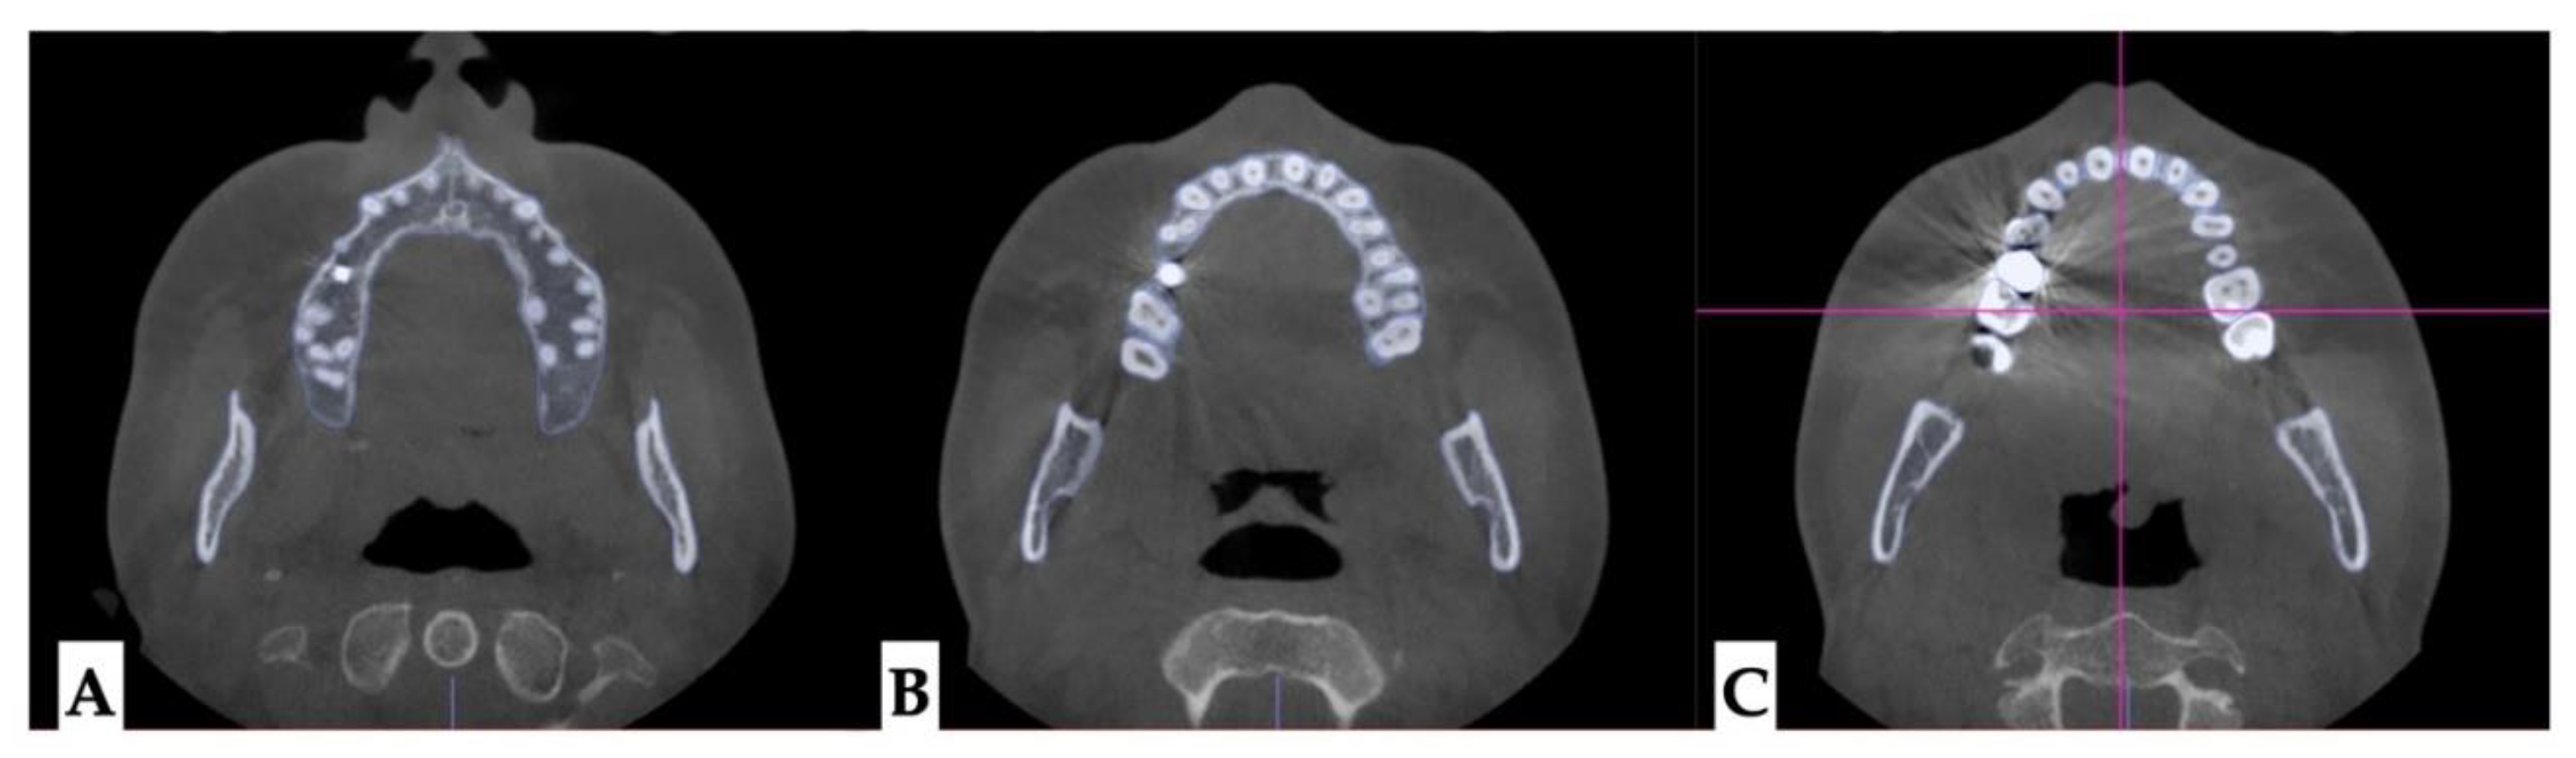

Dento-alveolar analysis: dento-alveolar slicing was performed at different levels of the maxillary teeth roots (apical third, half of the root length, and lower third of the root length) to evaluate the symmetry of root positions relative to the buccal cortical plate of the maxillary alveolar process. Upper left quadrant showed clear asymmetry of the root positions with the closer proximity to the buccal cortical plates. (Figure 5 and Figure 6). Palatal plane orientation before treatment is parallel to the constructed Orbital plane as seen on Figure 6, while the maxillary occlusal plane shows definitive canting with the left side occlusal plane located below the right side.

Figure 5. Pre-treatment axial plane slices visualization: A- axial slice at the level of the ANS with the skull oriented to all three reference planes, this view shows closer proximity of the root arises of the left upper quadrant to the buccal cortical plate of the alveolar process, B - axial view in the same orientation at the level of the 1/2 root length following the same pattern of buccal cortical plate proximity of the UL maxillary roots, C - ANS-PNS and Orbital planes orientation at the level of the lower 1/3 of the root length.

Figure 6. Pre-treatment axial plane slices visualization: A- axial slice at the level of the ANS with the skull oriented to all three reference planes, this view shows closer proximity of the root arises of the left upper quadrant to the buccal cortical plate of the alveolar process, B- ANS-PNS and Orbital planes orientation at the level of the lower 1/3 of the root length, both views showing asymmetry in UL roots positioning relative to the constructed circle with vertical diameter coinciding with the ANS-PNS plane.

Present study focuses on pre-treatment diagnosis and evaluation for the presence of pre-existing asymmetries and analysis of the asymmetric expansion outcome. As seen from the initial evaluation, patient presented with facial asymmetry related to both mandibular asymmetric position and narrow upper arch due to multiple dento-alveolar deformations and microdentic teeth. Initial root orientation was evaluated as a part of staged analysis, and revealed differential root inclination of the maxillary incisors relative to the buccal cortical plate of the maxillary alveolar process. Root proximity and higher buccal root torque of all maxillary incisors with left incisors being in closer proximity compared to the right side was one of the predisposing factors to pre-existing asymmetry of the maxillary anterior alveolar process in axial plane.